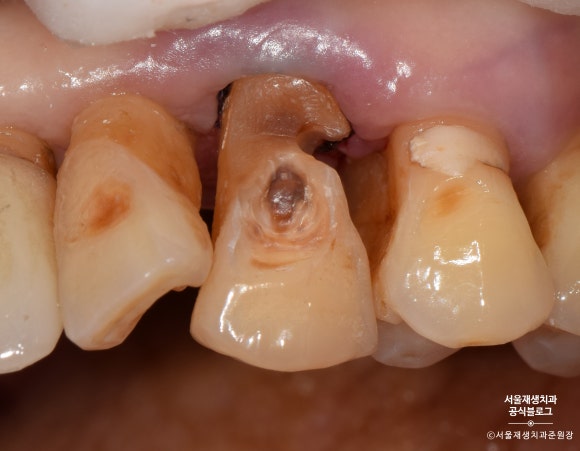

앞니에 생긴 마모증을 오랜기간 방치하여

큰 충치가 생긴 사례입니다.

치아의 목 부분, 다시 말해 잇몸과의 경계 부위에

짙은 오렌지색의 띠가 보이시나요?

치아의 겉면은 하얗고 투명한 법랑질인데 반해,

치아의 속살은 노랗고 불투명한 상아질입니다.

법랑질이 모두 마모되어 상아질이 노출되었고,

법랑질에 비해 무른 상아질이 안으로 파고들듯이 마모되고 있는 상태였습니다.